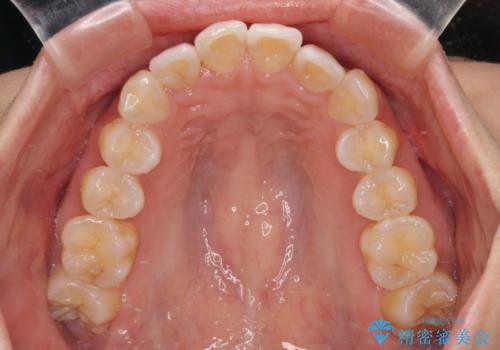

前歯のデコボコを治したい インビザライン矯正

- 上下前歯の叢生を気にして来院された患者様です。

インビザラインでの治療を希望されていて、デコボコの程度が中等度であり、安価なパッケージにて対応可能と判断されたため、インビザライン・モデレートを用いて矯正治療を行うこととしました。

インビザライン・モデレートは、製作できるアライナーの枚数に制限があるため、移動可能な量に限りがあるものの、インビザライン・ライトよりも枚数が多いため、幅広い症例に対応可能です。